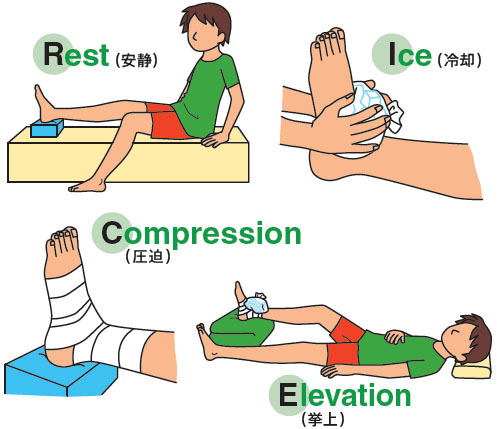

捻挫(ねんざ)したらどうする? 捻挫(ねんざ)は、とくに足首や指に起こりやすく、関節をひねって痛めてしまうことで起こります。 靭帯の損傷などが考えれらる場合は、整形外科での治療が必要です。 目立った腫れやひどい痛みといった症状がなければセルフケアで様子をみてもよいでしょう。 捻挫(ねんざ)直後の応急処置や、その後の手当についても · 特に応急処置の際、捻挫の患部に温湿布を貼ることは禁物です。 軽度の捻挫でも、しばらくは飲酒、湯船に浸かる入浴、運動などは避けましょう。 また、立ち仕事も数日は控え、医師の指示に従いながら再開するようにしましょう。2601 · 足首の外側が痛む場合は、 湿布を半分に折って中心部分に切れ込み をいれましょう。

捻挫処置の基本riceとは スノーボードにおける怪我と治療 スノーボード All About

捻挫で湿布を使用する期間はいつまで? 冷やす温めるが大切です! スポンサーリンク 捻挫というのは靭帯が損傷する怪我です。 靭帯を損傷すると痛みだけでなく、腫れや内出血を伴いこともあります。 きちんと処置することによって早期完治だけでなく再発を防ぐことや癖になることを防ぎます。 この場合に湿布を使用する期間というのはいつまででしょうか